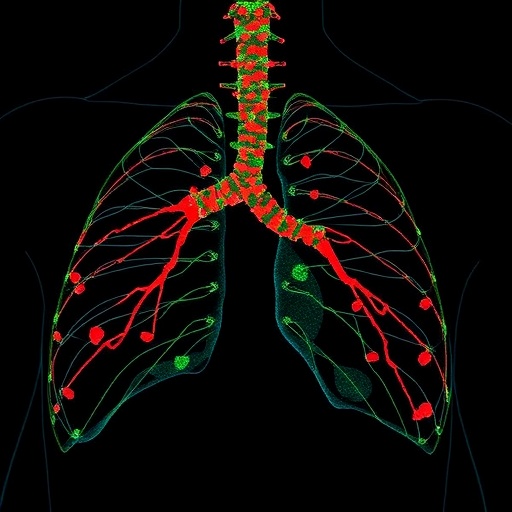

In the relentless search for reliable cancer biomarkers, a groundbreaking study has illuminated the role of circulating Heat Shock Protein 70 (Hsp70) as a pivotal indicator of tumor progression and relapse in thoracic cancers. Thoracic malignancies, notably non-small cell lung cancer (NSCLC), remain among the leading causes of cancer-related mortality worldwide. Their insidious capacity for early metastasis and therapeutic resistance has posed formidable challenges to clinicians and researchers alike. The latest research published in BMC Cancer unveils the intricate relationship between extracellular Hsp70 levels in patient plasma and the aggressiveness of thoracic tumors, marking a potential paradigm shift in how oncological prognostication and treatment monitoring may be approached.

Heat Shock Protein 70, a molecular chaperone with well-documented cytoprotective functions, is frequently overexpressed across a spectrum of malignant tissues. Unlike its intracellular counterpart, the membrane-bound form of Hsp70 (mHsp70) uniquely adorns the plasma membrane of tumor cells but is conspicuously absent from normal cell membranes. This aberrant membrane localization is not merely a passive biomarker but actively associates with tumor advancement and resistance to conventional therapies. Intriguingly, viable tumor cells expressing mHsp70 release extracellular vesicles—specifically microvesicles—that carry this protein into the circulation, offering a measurable footprint of tumor activity accessible through minimally invasive blood sampling.

Findings revealed a stark elevation in circulating eHsp70 concentrations in NSCLC patients relative to healthy controls, underscoring its potential as a discriminative biomarker. Importantly, no significant difference in eHsp70 levels was observed between the adenocarcinoma and squamous cell carcinoma subtypes, suggesting a pan-NSCLC relevance of this marker. The study also demonstrated a stepwise increase in eHsp70 in parallel with advancing clinical stages culminating in metastatic disease, reflecting an ongoing escalation of tumor burden and aggressiveness.

Among the most salient discoveries was the association of heightened eHsp70 levels with lymph node metastases—a critical prognostic factor in thoracic oncology. Patients with nodal involvement exhibited markedly higher plasma eHsp70, reinforcing the protein’s utility in detecting early metastatic spread that might otherwise evade conventional imaging modalities. This correlation extends the utility of eHsp70 from an indicator of tumor presence to a marker distinguishing more advanced disease states, thus empowering clinicians with actionable insights prior to surgery.

Crucially, elevated pre-surgical eHsp70 levels were strongly predictive of early disease relapse following ostensibly curative resection. This insight is transformative, offering a non-invasive biomarker to stratify patients at highest risk for therapeutic failure and recurrence, thereby enabling intensified surveillance or adjunct treatment strategies. Early identification of such patients could streamline precision oncology workflows, curtailing morbidity and improving survival outcomes.

Contextualizing these findings within the broader landscape of thoracic oncology, circulating eHsp70 emerges as a multifaceted marker that encapsulates tumor biology, metastatic potential, and immune dysregulation. Its measurement could complement imaging and histopathological assessments, potentially serving as a cornerstone in individualized patient management algorithms. Moreover, its predictive capability for early relapse positions it as an indispensable tool in post-surgical patient stratification.